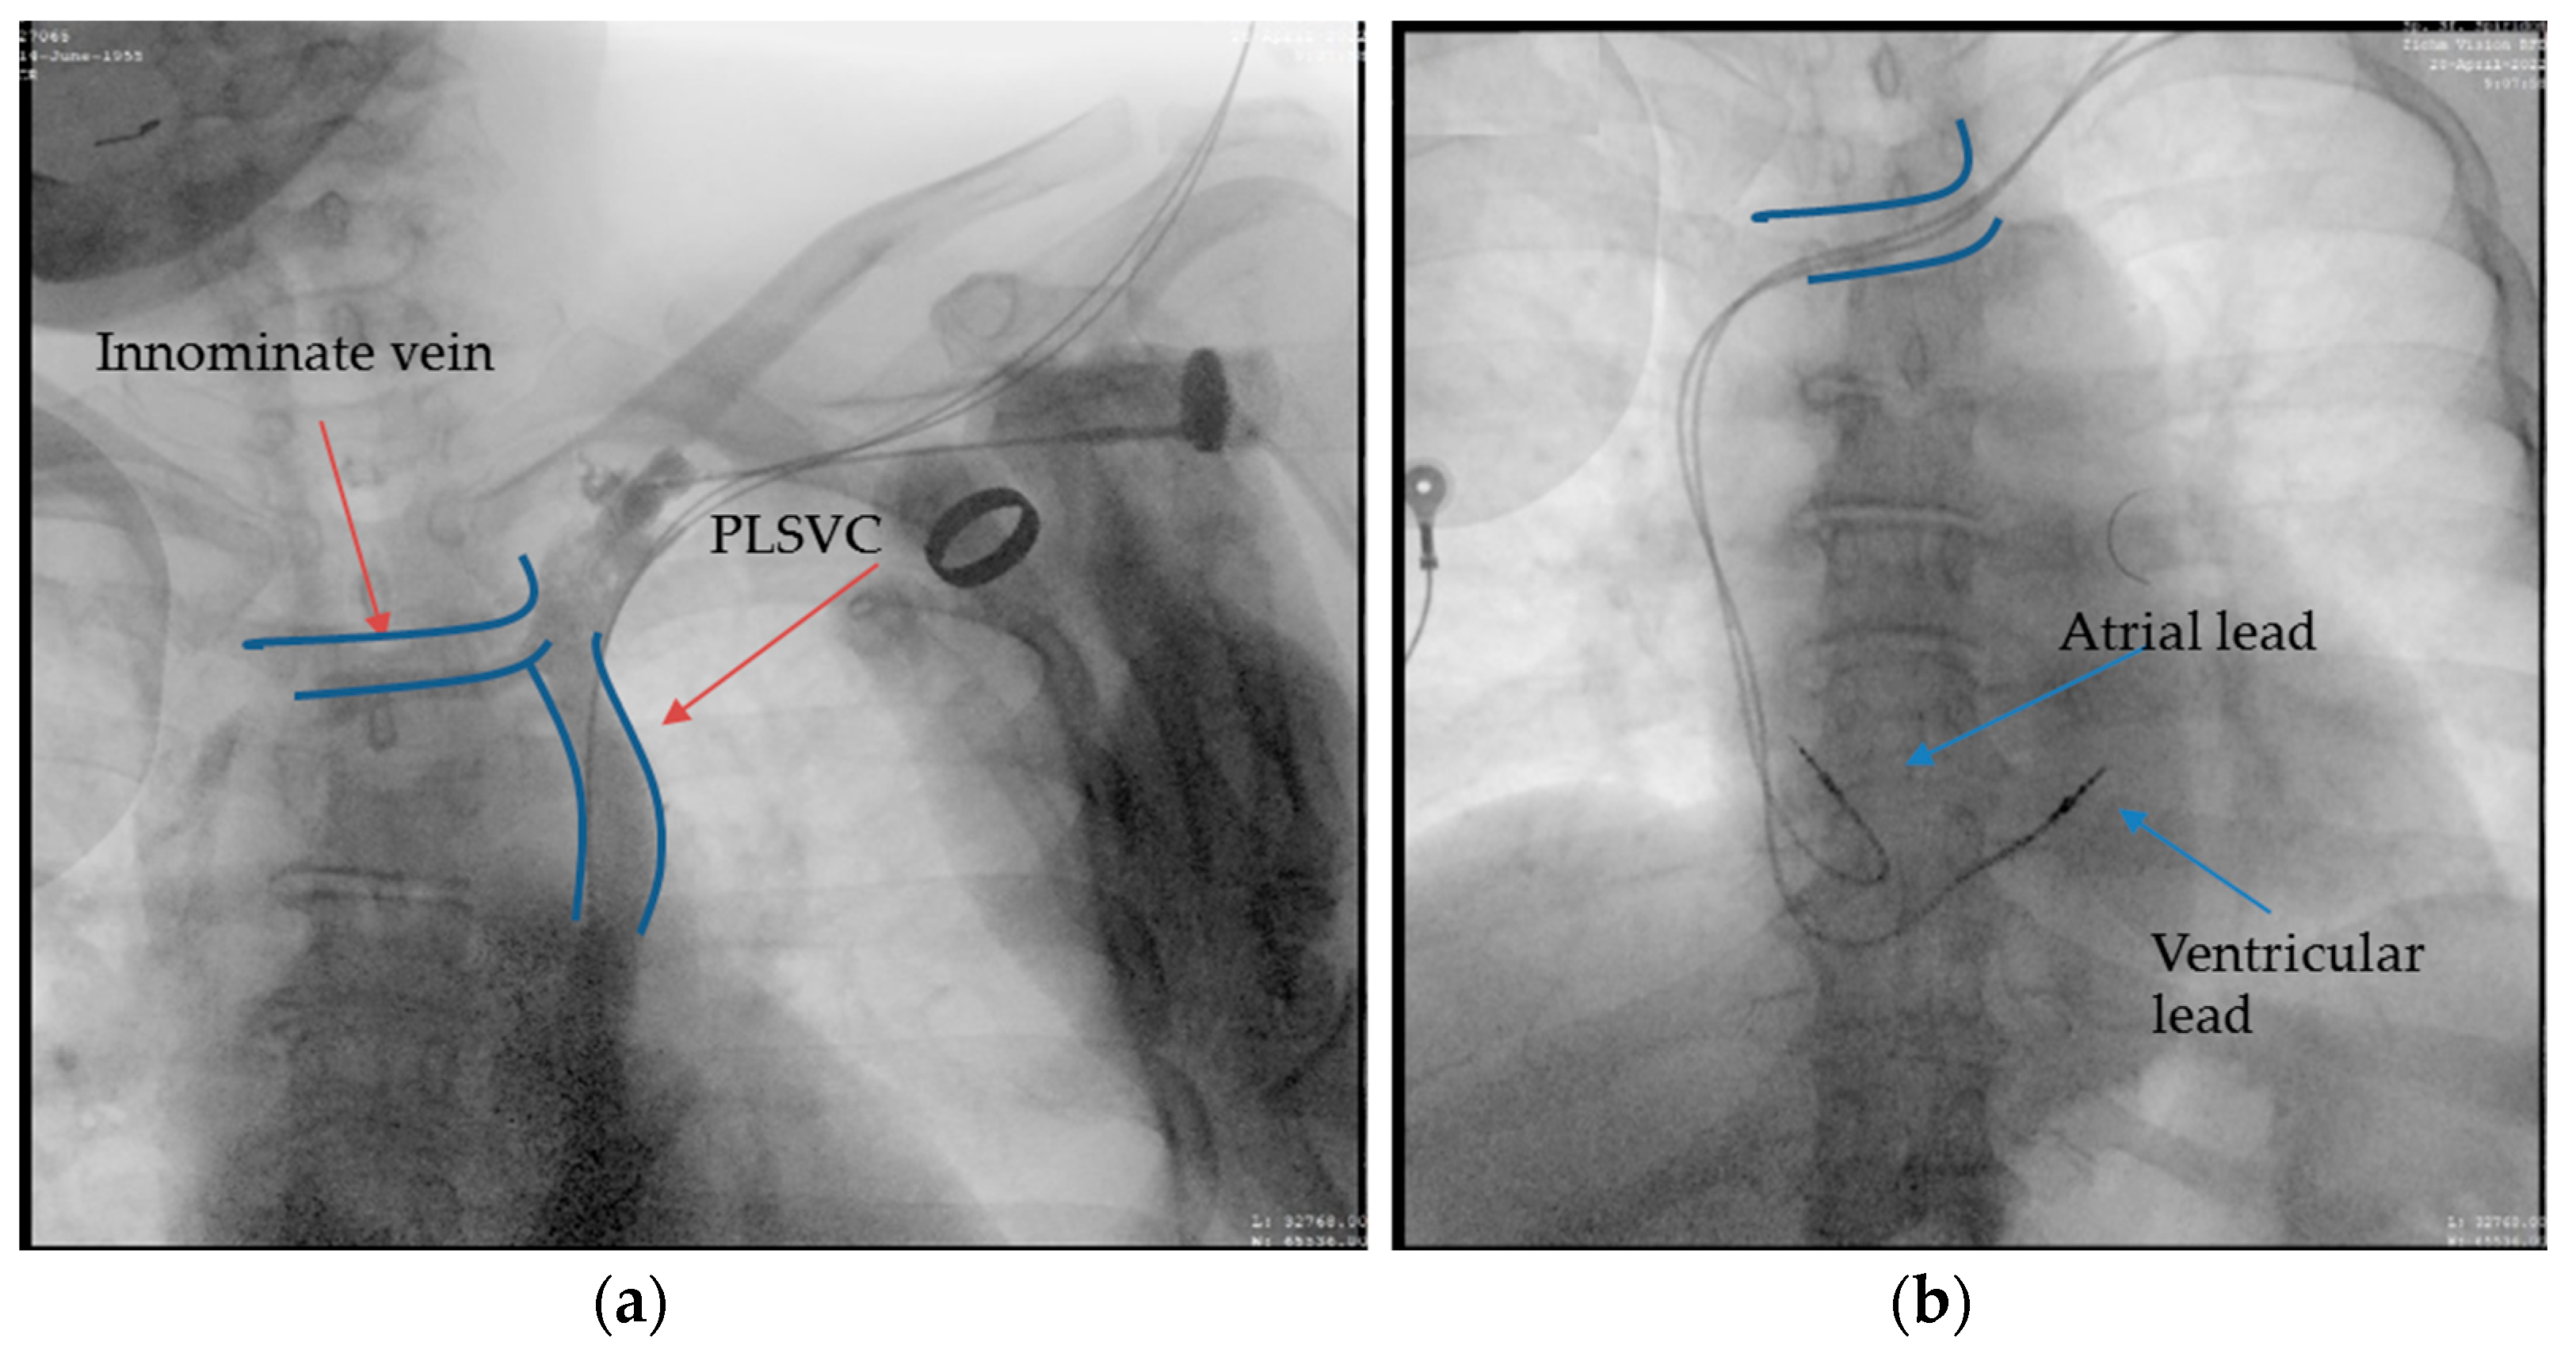

A 66-year-old female patient diagnosed with sick sinus syndrome (tachycardia–bradycardia syndrome: sinus bradycardia alternating with paroxysmal atrial fibrillation (AF)), based on 24 h ECG Holter monitoring, symptomatic through repetitive syncope, fatigue, and palpitations, was referred to our clinic for the implantation of a pacemaker. During the dual-chamber pacemaker implantation, the abnormal route of the guide wires was noticed, and we decided to perform a venography through the subclavian vein already punctured (Figure 3a). This not only confirmed the presence of persistent left superior vena cava, but also a communication with the right superior vena cava through a small vein called the innominate vein (type IIIa). Faced with this situation, we decided to approach this small caliber vein to facilitate the implantation of the leads without passing through the coronary sinus. First of all, we managed to insert the guide wires into this vein using rotational movements, and for the leads we used a straight stylet. After reaching the atrium, we passed the tricuspid valve with a specific stylet, and the lead was placed at the right ventricular septum. Finally, the second lead was placed in the right atrial appendage (RAA) (Figure 3b). A thoracic angio-CT was performed, to better characterize the venous anomaly (Figure 4).

Figure 3.

Atrial and ventricular lead placement through innominate vein, right superior vena cava, right atrium, and ventricle: (a) the contrast injection in the left subclavian vein showing the presence of PLSVC and innominate vein, which ensures communication with right superior vena cava; (b) the final result after we placed the leads at the level of the right atrium (RAA) and right ventricular septum approaching the innominate vein and avoiding the coronary sinus.

Figure 4.

Coronal section. The yellow arrows: the lead in the subclavian vein, persistent left superior vena cava, the innominate vein, and the right superior vena cava. The blue arrow: the right brachiocephalic vein.